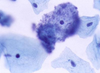

1

Q

A

1 Trichomonas vaginalis